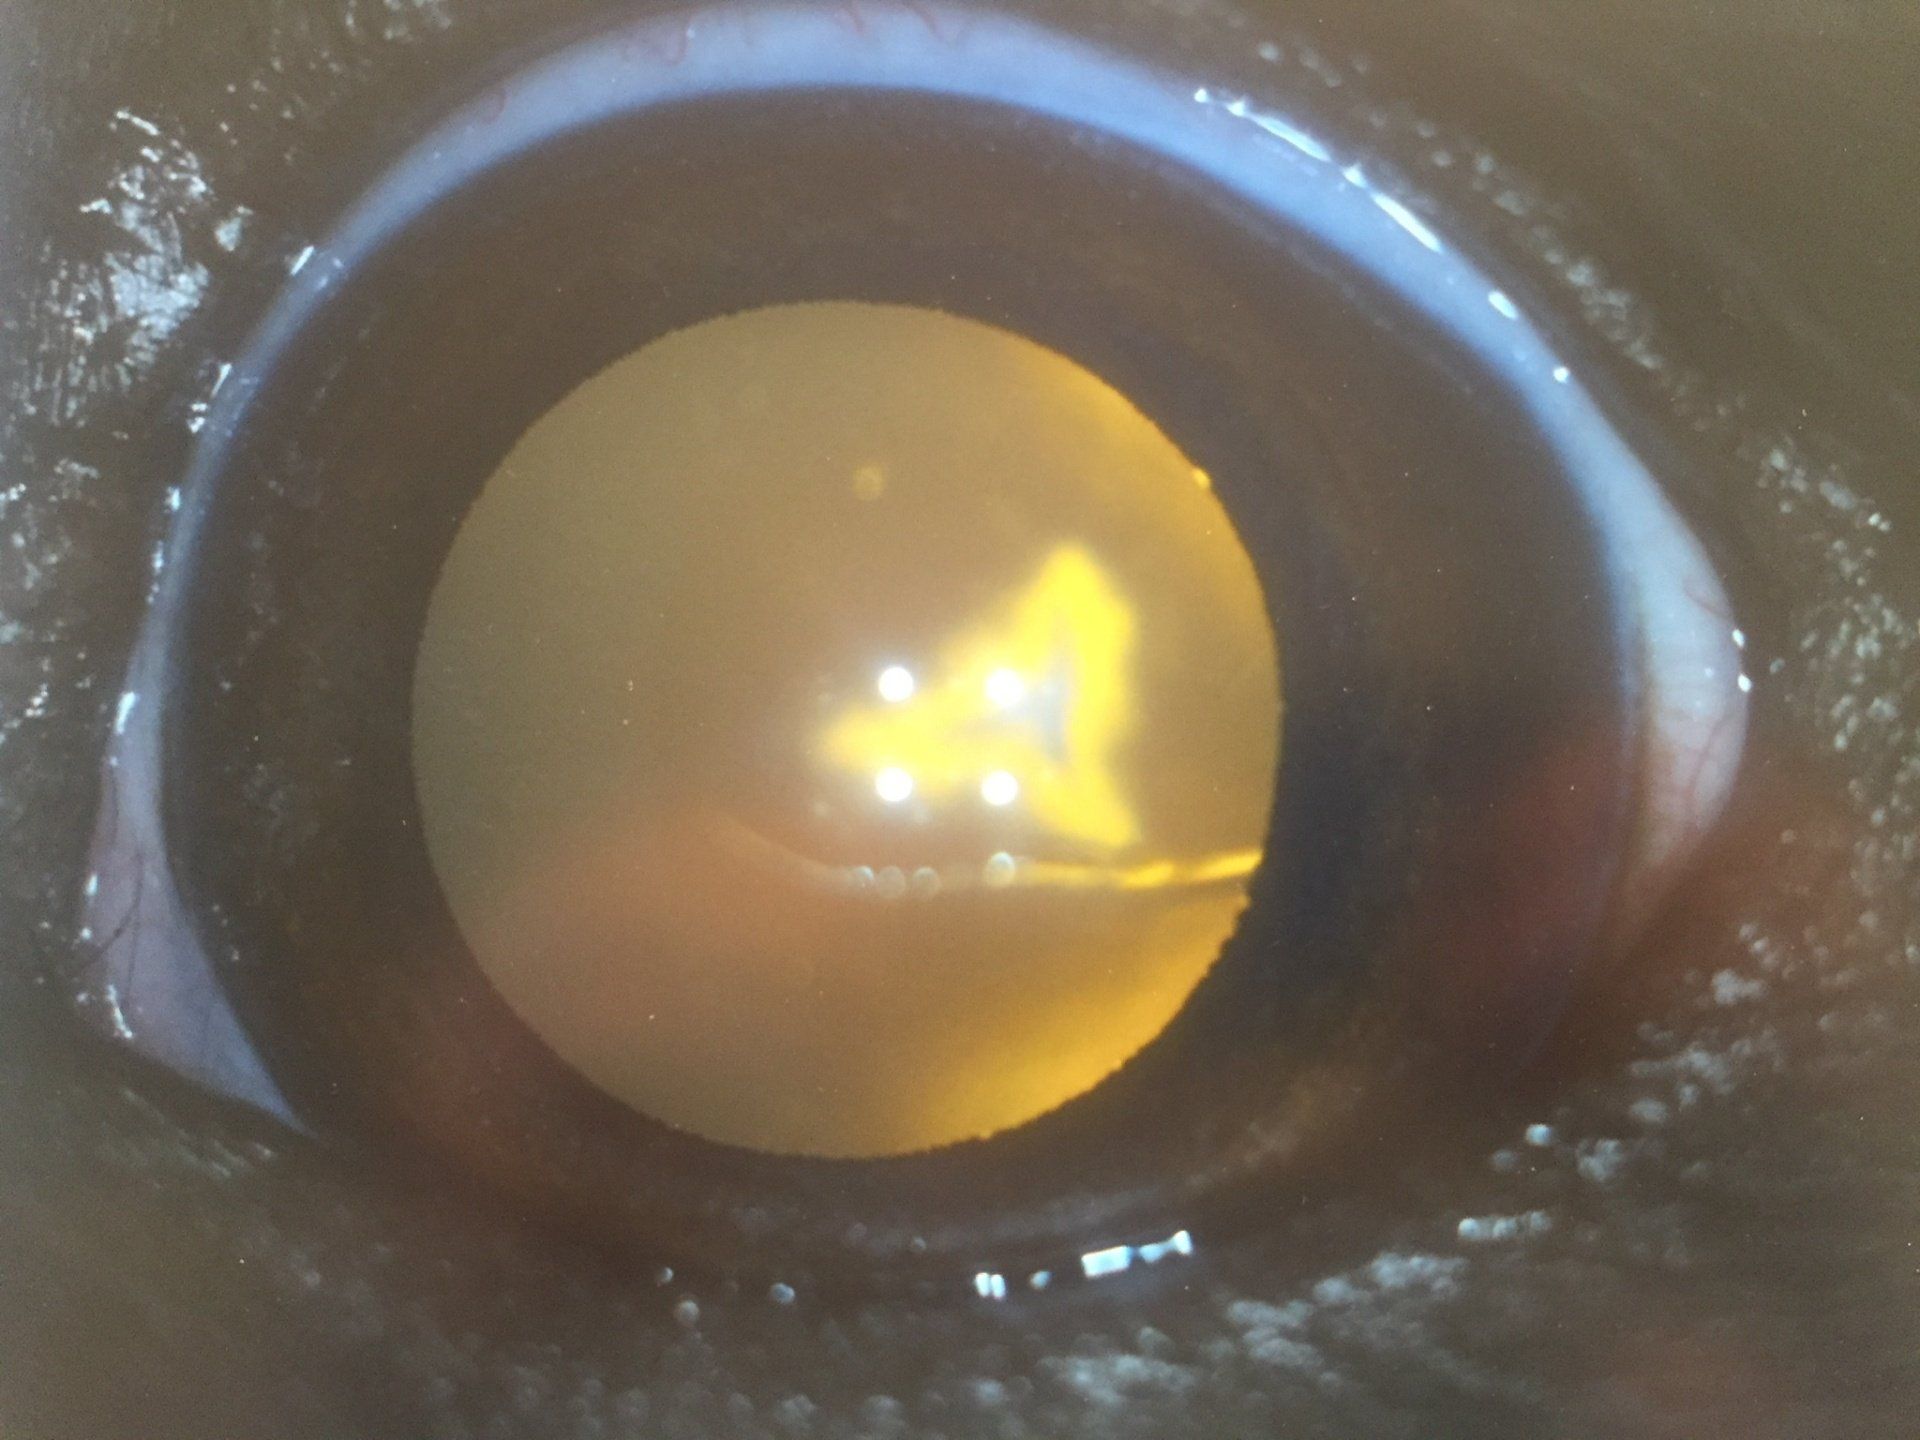

- Cataract phacoemulsification surgery and IOL insertion performed by our visiting cataract surgeon, George Peplinski

Cataracts

Cataracts may affect all species. The predominantly affected species in veterinary medicine is the dog. Cats, rabbits and horses are presented less frequently. Read more...